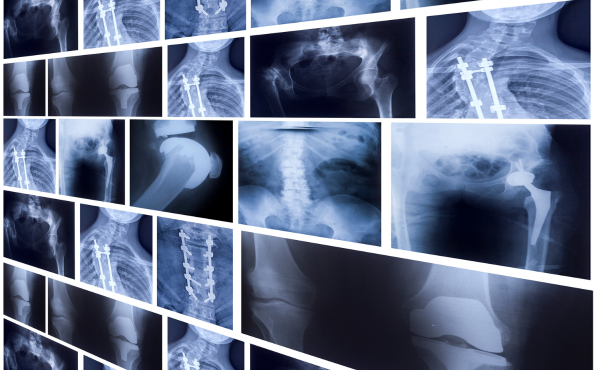

X-Ray Services Offered at Purva Hospital

Chest X-Ray – To detect lung infections, pneumonia, tuberculosis, or heart-related issues.

Bone & Joint X-Ray – For fractures, dislocations, arthritis, and joint pain assessment.

Spine X-Ray – For back pain, slipped disc, and posture-related issues.

Abdominal X-Ray – To check for kidney stones, intestinal blockages, or digestive problems.

Skull & Facial X-Ray – For head injuries, sinus infections, or dental issues.

Soft Tissue X-Ray – To detect tumors, foreign objects, or swelling in soft tissues.